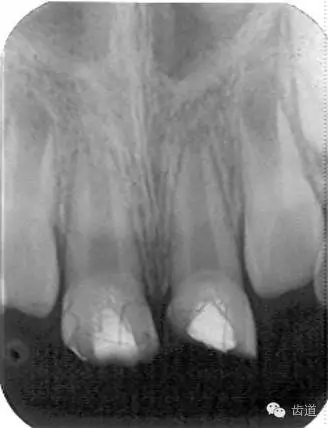

3個月左右在X線片上可觀察到修復(fù)性牙本質(zhì)層的出現(xiàn), 術(shù)后6個月左右,??捎^察到連續(xù)的有一定厚度的修復(fù)性牙本質(zhì)層; 修復(fù)性牙本質(zhì)層的出現(xiàn),是間接牙髓治療成功的重要指征。

牙本質(zhì)橋形成 formation of dental bridge

恒牙繼續(xù)發(fā)育 developing of permanent tooth